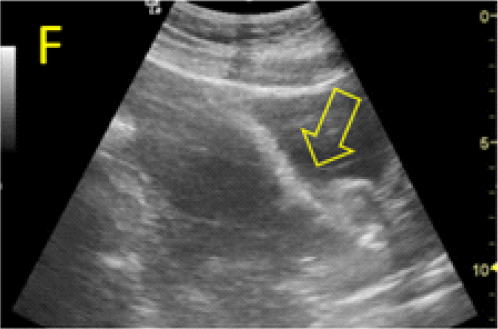

Dilatation and curettage (D&C) under ultrasound guidance was proposed for a safe, precise and rapid evacuation of the gestational sac. In order to further avoid bleeding complications, angiographic investigation of the pregnancy site was re-scheduled and performed 24 hours prior to the surgical evacuation of the CSP, due to the potential degradation of the embolic material and secondary revascularization. Indeed, a significant flow was identified, and bilateral re-embolization was performed. The cervical dilation and pregnancy aspiration were performed under sonographic guidance (Figure 5, A-D). In our opinion, the careful and complex management was very important, as the bladder-uterine interface appeared severely damaged, with the easily translation of the bladder wall inside the isthmic uterine segment through the scar area when the pregnancy war evacuated by aspiration (Figure 5, E-F).

Figure 5. Cervical dilation and pregnancy aspiration performed under transabdominal sonographic guidance. A: the appearance before the procedure, the gestational sac bulging in the urinary bladder is marked with open star. B:Cervical dilation, the metallic Hegar dilator is indicated with open arrow. C, D: progressive aspiration of the pregnancy. E, F: translation of the posterior bladder aspect (open arrow) inside the isthmic uterine segment, through the pregnancy scar area, at the time of aspiration.